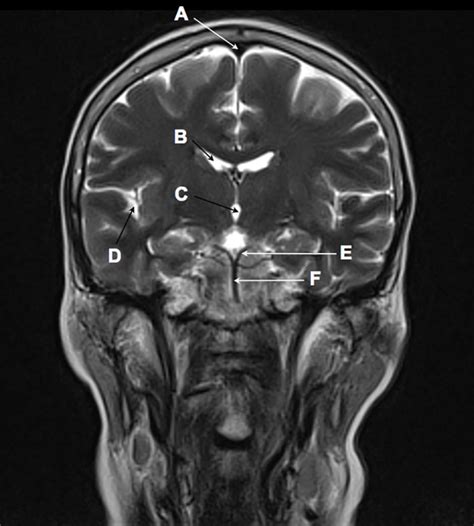

Understanding the intricacies of the human brain is a complex yet fascinating endeavor. One of the most revealing perspectives in neuroimaging is the coronal view of the brain. This view provides a cross-sectional image that cuts through the brain from front to back, offering insights into the brain's structure and function that are not readily apparent from other angles.

The coronal view of the brain is a vertical slice that divides the brain into front and back sections. This view is particularly useful for visualizing the brain's internal structures, such as the ventricles, the corpus callosum, and various lobes. By examining the brain in this orientation, neurologists and researchers can gain a deeper understanding of how different regions of the brain interact and function.

Key Structures Visible in the Coronal View

The coronal view reveals several key structures within the brain. Some of the most important ones include:

• Ventricles: These are fluid-filled cavities within the brain that help cushion and protect it. The lateral ventricles, third ventricle, and fourth ventricle are all visible in the coronal view.

• Corpus Callosum: This is a thick band of nerve fibers that connects the left and right hemispheres of the brain, facilitating communication between them.

• Lobes of the Brain: The frontal, parietal, temporal, and occipital lobes can be clearly seen in the coronal view, each responsible for different functions such as motor control, sensory processing, language, and vision.

Interpreting Coronal View Images

Interpreting coronal view images requires a deep understanding of brain anatomy and pathology. Here are some key points to consider:

• Symmetry: The brain is generally symmetrical, so any asymmetry in the coronal view may indicate an abnormality.

• Ventricle Size: Enlarged ventricles can indicate conditions like hydrocephalus or atrophy.

• White Matter Lesions: These can be signs of conditions like multiple sclerosis or small vessel disease.